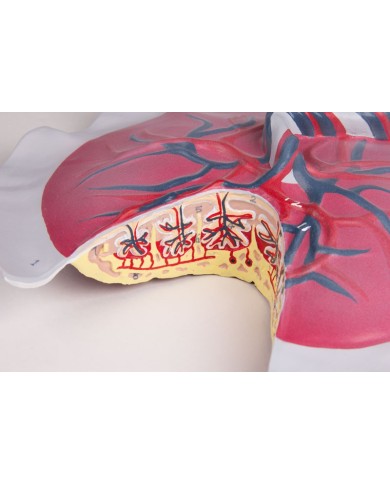

Questo modello dettagliato mostra, oltre alle strutture anatomiche del cuore, anche una parte del diaframma (base)

Realizzato in stampa 3D ad elevatissima risoluzione a colori.